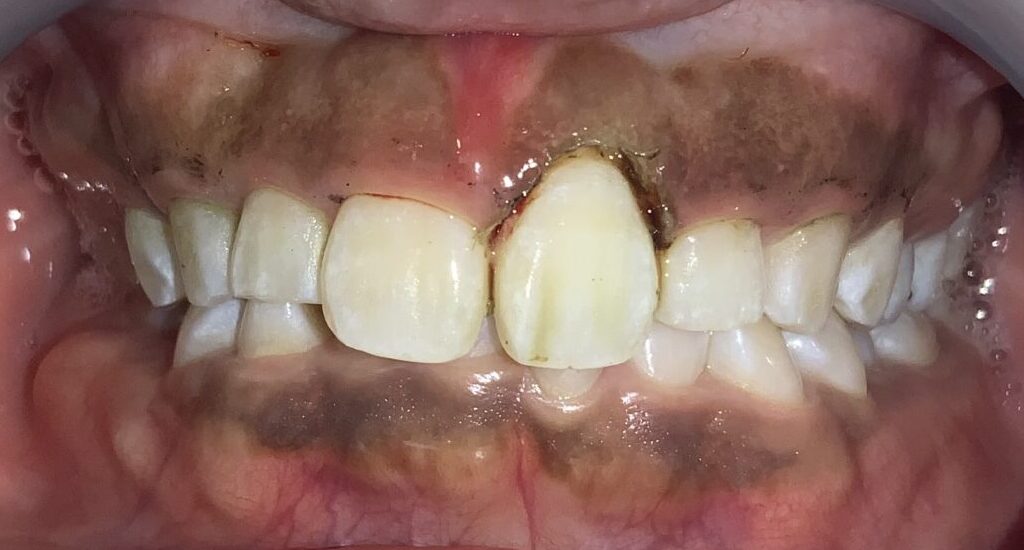

難関の犬歯を超えたところで、第一小臼歯の4番面の歯を検査します。

奥歯なのに、歯ぐきがたくさん被っているようです。3番目の犬歯と違い、奥歯の形になってきている4番目の歯は、犬歯とは違う注意が必要です。

この歯は奥歯の形なので、歯ぐきを取りすぎると、知覚過敏になる場合があります。また、前歯と奥歯の間の歯ですから、前歯に比べて治りが遅い傾向にあります。歯ぐきの切除も慎重に行わなければなりません。

犬歯です。

歯ぐきの部分が大きいですね。しかも歯ぐきが薄いので、検査器具が歯ぐきの下から透けています。

最後に4番目の歯です。

1本1本、歯ぐきの被り方や厚みは違いますから、その点を見極める診察が大切です。